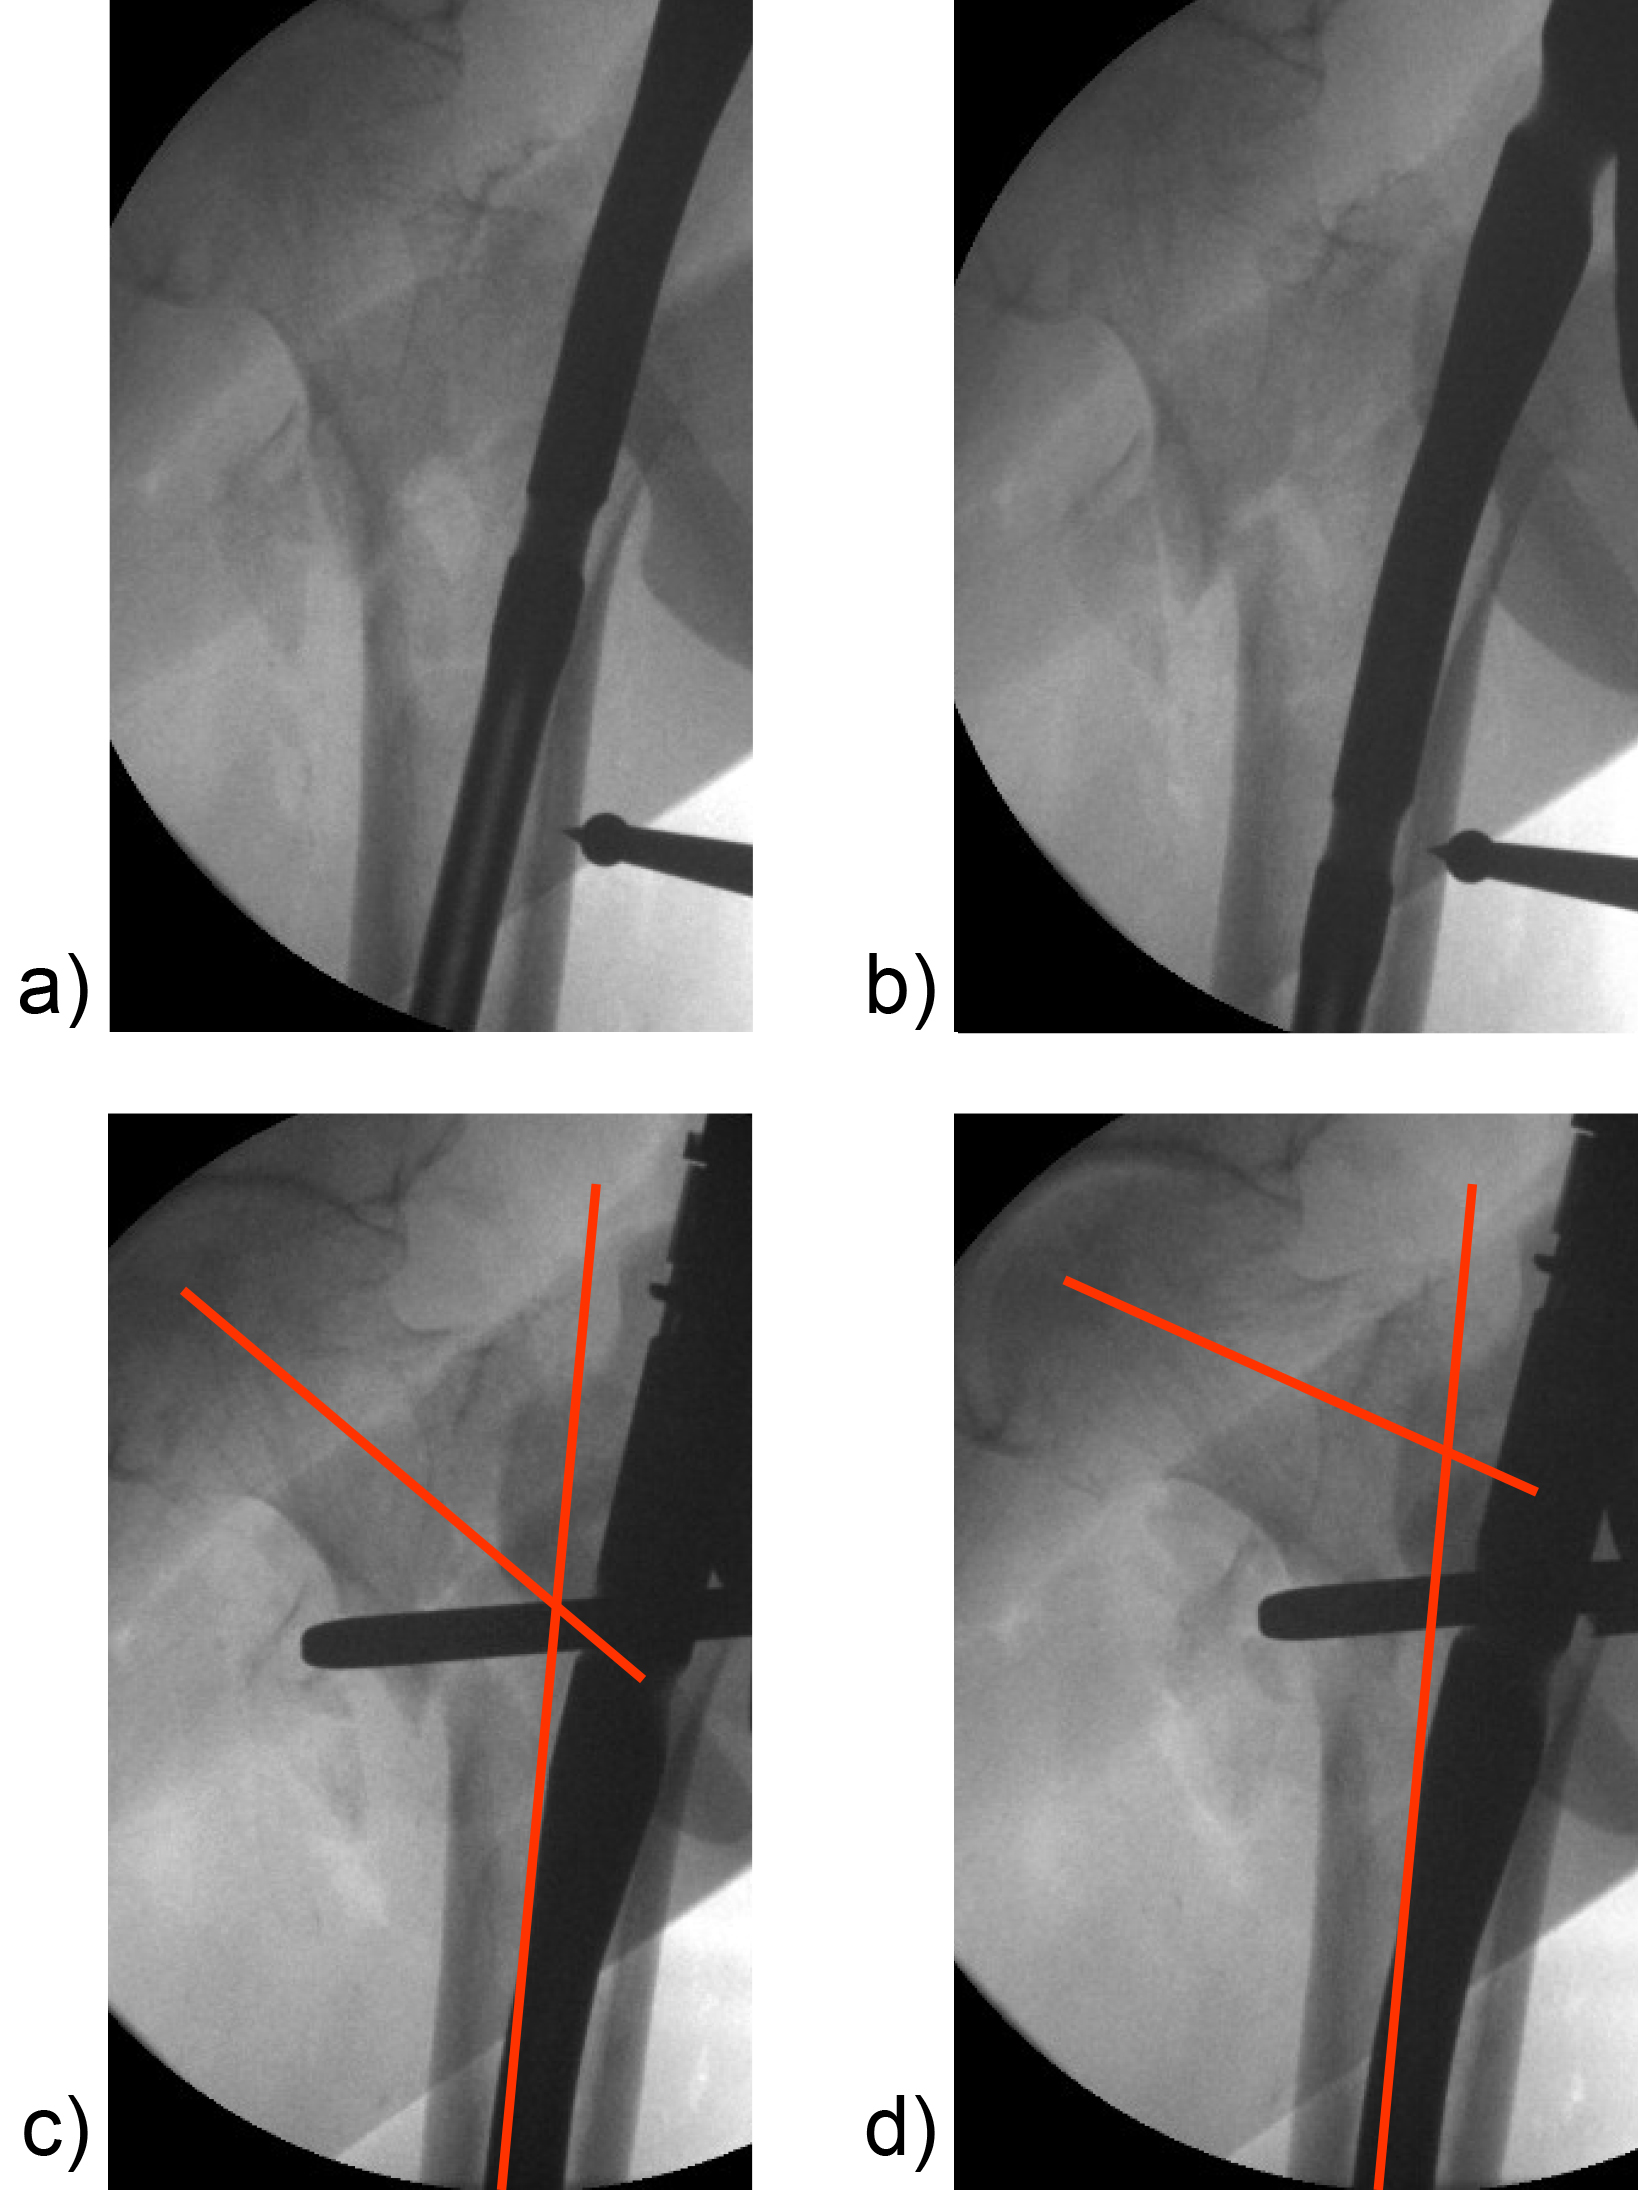

Hollow reamer

When the TFN-Advanced proximal femoral nailing system was launched in 2015, flexible and solid drill bits were offered to prepare the entry path of the nail. When fracture lines are located in the area of the intended nail insertion point, fracture fragments can be pushed apart when introducing these drill bits through the fracture lines causing a varus malreduction of the head-neck fragment. In order to avoid this clinical problem, an optional hollow reamer has been developed (Fig 5).

When using the hollow reamer, fracture fragments are not displaced because the instrument facilitates the removal of a cylindrical bone plug from the insertion area (Fig 6) without causing radial displacement forces to the surrounding bone.

Curved elevator and L-shaped elevator

Reduction in certain proximal femoral nailing cases still remains a clinical challenge. Surgeons from Japan especially emphasize the importance of anatomical reduction of the medial and anterior cortices to improve the stability of the fracture and the efficacy of the nail. With no bone support at the medial and anterior cortices there is a higher risk for shortening of the femoral neck and fixation failure.

Because of the need for dedicated reduction instruments to facilitate the required reduction maneuvers, two new instruments have been developed: the curved elevator (Fig 7) and the L-shaped elevator (Fig 8).

The curved elevator is intended to align shifted fragments in the proximal femur through a lateral or an anterior approach (Fig 9). The recommendation is to obtain an extramedullary type of reduction with good bone support.

The L-shaped elevator is radiolucent. This elevator is usually applied for the reduction of strong anteversion in the lateral view (Fig 10).